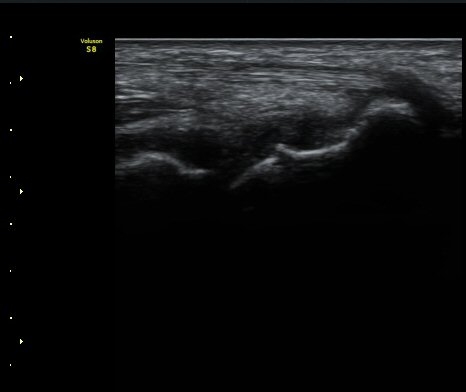

ÃÊÀ½ÆÄ °Ë»ç

¼Õ¸ñÀÇ Á¾´Ü

ÁÖ»ó°ñ ¼±»ó°ñÀýÀº ´Ü¼ø¹æ»ç¼± ÃÔ¿µ ½Ã È®ÀεÇÁö ¾ÊÀº °æ¿ì°¡ ¸¹Àºµ¥ ÀÌ ¶§ ÃÊÀ½ÆÄ

°Ë»ç°¡ ÁÖ»ó°ñ °ñÀý Áø´Ü¿¡ ¸Å¿ì À¯¿ëÇÏ´Ù. ±×·¯¹Ç·Î ¼Õ¸ñ ´ÙÄ£ ÈÄ Áö¼ÓÀûÀÎ ÅëÁõÀ»

È£¼ÒÇϰí ÁÖ»ó°ñ ºÎÀ§ ¾ÐÅëÀ» º¸ÀÌ´Â °æ¿ì ÃÊÀ½ÆÄ°Ë»ç¸¦ ½ÃÇàÇÏ¿© ÁÖ»ó°ñ °ñÀý ¿©ºÎ¸¦

È®ÀÎÇØ¾ß ÇÑ´Ù.

ÃÊÀ½ÆÄ°Ë»ç¸¦ ½ÃÇàÇÒ ¼ö ¾ø´Â °æ¿ì´Â ÄÄÇ»ÅÍ ÃÔ¿µ°Ë»ç¸¦ ÁÖ»ó°ñ °ñÀýÀ» È®ÁøÇÒ ¼ö ÀÖ´Ù.